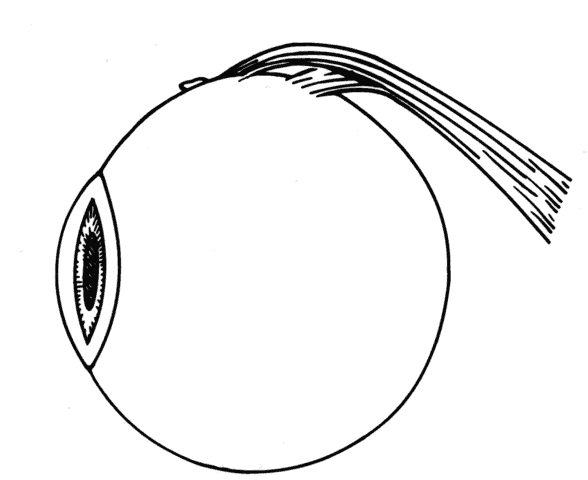

Reintervention to correct strabismus is indicated if a technical problem occurred immediately after the initial procedure. A muscle that has become disinserted or is “lost” postoperatively requires immediate exploration and correction of the problem (Figs. 2 and 3). A similar situation may occur when a previously operated muscle retracts ("slips") inside the muscle capsule (Fig. 4). The slipped muscle will appear paretic, and early surgical intervention should be considered. The clinical pictures of these technical failures are very similar. There is poor function of the affected rectus muscle, and the induced strabismus will be noncomitant. Operations may be performed on the incorrect eye muscles or eye (Fig. 5). If this occurs, reoperation should not be delayed.

Fig. 2. This 8-year-old patient had her lateral rectus recessed 4 days before referral. Twenty-five prism diopters of esotropia and absent abduction were noted. The insertion was “empty” in appearance, and an untied suture could be visualized underneath the conjunctiva (arrow).

Fig. 3. This diagram demonstrates the findings of surgical exploration of the patient in Figure 2.